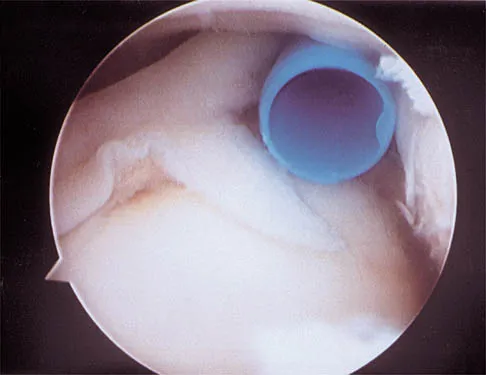

A 21-year-old collegiate pitcher has had pain in his dominant shoulder for the past 3 months despite management consisting of rest, rehabilitation, and an analysis of throwing mechanics. An arthroscopic photograph from the posterior portal is shown in Figure 10. The biceps anchor to the bone was not detached to probing. Treatment of the lesion to the left of the cannula should consist of arthroscopic

Explanation